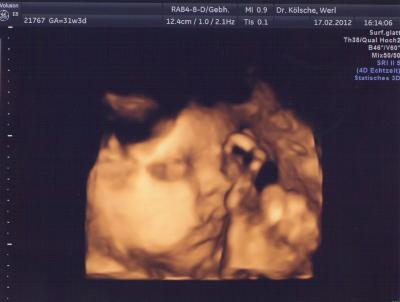

Meine Püppi :)

Guten Morgen meine Lieben!! Endlich komme ich mal wieder zum schreiben ,hab drei Tage Karneval hinter mir und nun bin ich einfach nur platt .Aber es war super toll und ich hab echt super durch gehalten,Kostüm sahs auch super... Freitag hatte ich mal wieder Vu.Alles supie soweit ,Püppi liegt nun endlich in Startposition,was ich die letzten Tage auch deutlich gemerkt habe,Sie drückt echt schon nach unten.Jetzt kommt der Kracher sie soll angeblich 2100 Gramm wiegen ....wou,.. da hat sie sich aber die letzten zwei Wochen ganz schön was angefressen *lol*.Na ja mein fa ist sich jetzt nicht mehr so sicher mit dem Et,ob wohl der ja später nicht mehr korrigiert werden kann.Aber da mein Et nur laut der Größe errechnet wurde (weil ich meine letzte Mens nicht mehr wusste) ,kann wohl alles möglich sein. Auf jeden Fall hat sie ganz schöne Pausbacken und ein Doppelkinn Wir warten es ab.Mein Bauch hat auch eine sehr komische Form bekommen,wenn ich sitze ist er total platt...:D LG Vanessa+Emma

Hallo Vanessa, Schön, dass bei der VU alles okay war! Deine Bauchbilder sind ja wirklich "seltsam"; dass der Bauch vor 2 Wochen um einiges größer war als jetzt...... Aber man sieht, dass er definitiv weiter unten ist..... Das Babybildchen ist ja total süüüüß! Liebe Grüße Sonja